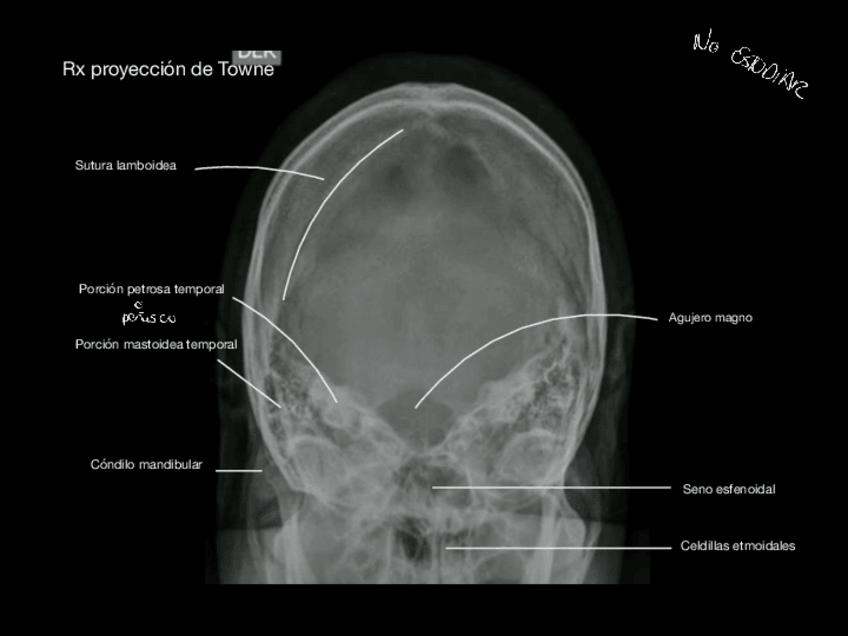

He publicado nuevos apuntes de Anatomía por la imagen: Laminas-craneo.pdf

7 páginas